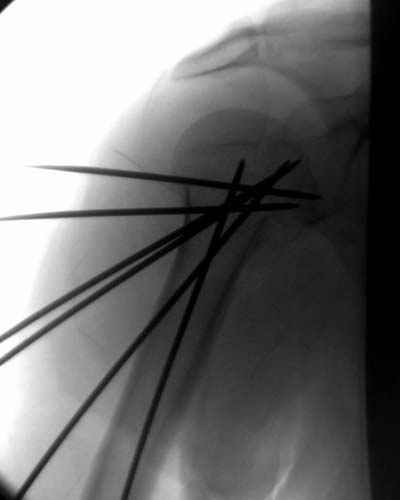

Здесь случай перелома-вывиха плеча, больному 56 лет, после "дважды" закрытой неудачной репозиции, опять же ургентно взяли в операционную, после полного общего обезболивания попытались сделать репозицию, и фиксацию провели спицами.

Больной находился в повязке, примерно напоминяющей косыночную, рекомендованы движения в локтевом суставе и маятниковые движения в плече, спицы удалены в три недели (были случаи миграции)

Да. У нас довольно скромный опыт такого остеосинтеза (по 2 случая - плечо и наружная лодыжка), дошли до использования самого простецкого троакара, через который мы сверлим кость и вводим 6 мм стержни, когда накладываем аппарат. Соответственно, в качестве забойника отлично работает любой стержень от аппарата Илизарова. Еще из наших туземных особенностей - страшная любовь к спицевым дистракторам, поэтому делали в нем. Результат у этой дамы неизвестен, т.к. она из области и уехала рожать сразу после остеосинтеза, сейчас прошло больше 5 месяцев...

Что-то, наверно, сделали мы не совсем оптимально, поскольку у Анатолия Федровича и его соратников как-то красивее "раскрываются" спицы в головке плеча - надеюсь, он прокомментирует и подскажет, что надо подправить.